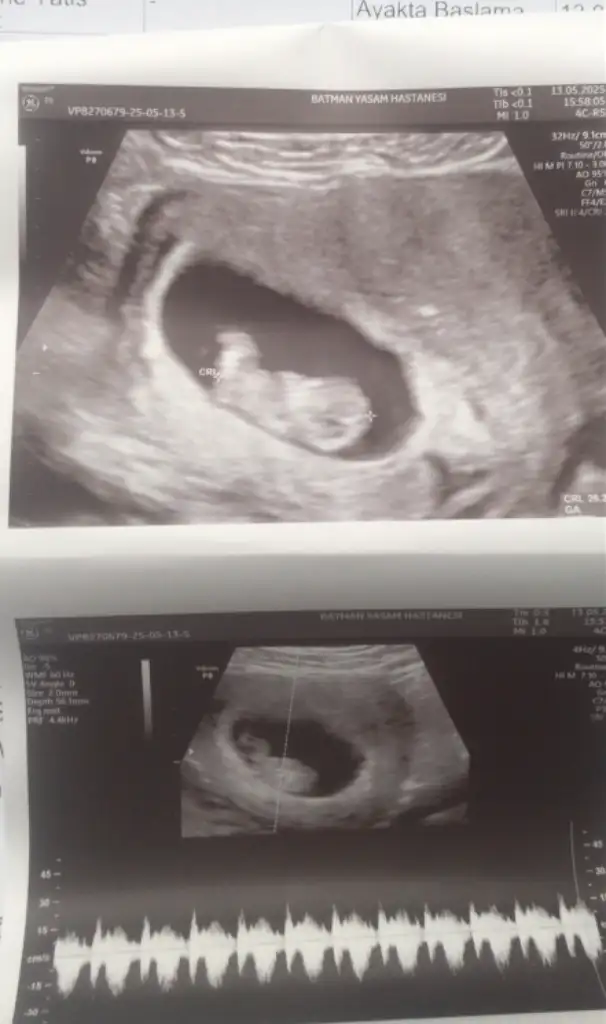

Banada tahminde bulunabilirmisiniz 10 hafta 4 günlük

• IMG_20250424_145427.webp

14,1 KB · Görüntüleme: 54

• IMG_20250424_145418.webp

19,3 KB · Görüntüleme: 45

• IMG_20250424_145414.webp

18,3 KB · Görüntüleme: 55